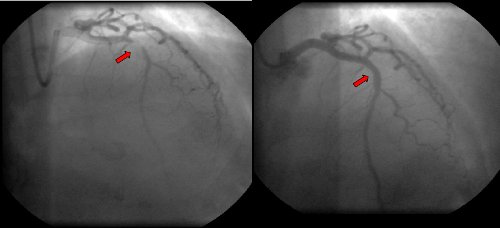

Se realiza CACG que evidencia lesión de 98% en tercio medio de ADA, la que se revasculariza con colocación de stent (figs. 8 y 9). La arteria coronaria derecha (CD) y la circunfleja (Cx) no presentan lesiones significativas.